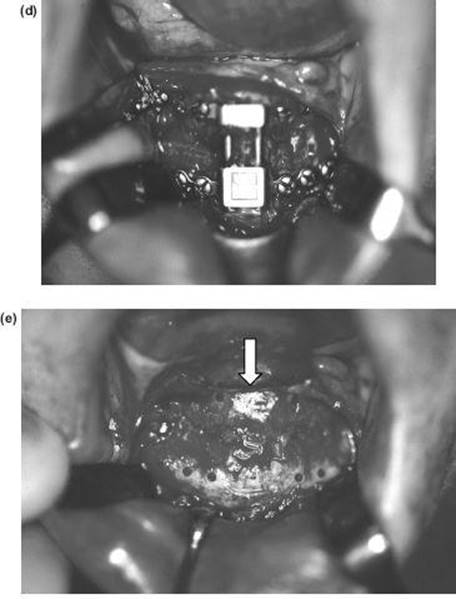

7. The nasal septum and pterygoid plates are separated intraorally, as in the Le Fort I operation.

8. If distraction osteogenesis is not being used, mobilisation is carried out extraorally from above and behind the head (“slowly but strongly”) with the Rowe's disimpaction forceps. Both a forward tilting and transverse rotation are required to achieve a completely mobile skeletal block. Intraoral traction with Tessier's maxillary retractors is also important.

9. Temporary intermaxillary fixation is applied, using an intermediate wafer in a bimaxillary case. The bone grafts are inserted at the osteotomy sites. The most important one is the malar cut, which is wedged open as shown in Figure 9.14 and fixed with bone plates.

10. All sharp bony margins are carefully masked with spare can-cellous bone or smoothed with an acrylic bur.

11. At this stage the intermaxillary fixation is removed and, where necessary, the mandibular osteotomy completed, drains inserted and the intraoral wounds sutured.

12. The pharynx is sucked out and the pack removed.

13. The blepharoplasty wounds are closed after the insertion of miniature vacuum drains, with subcuticular 5/0 Prolene sutures.